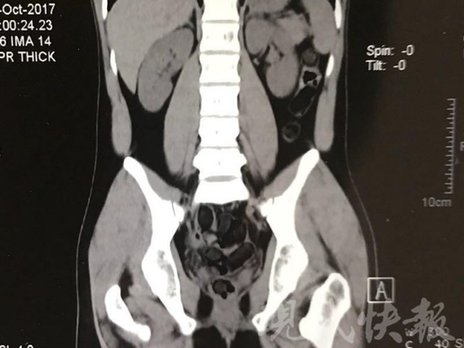

小伙體內(nèi)藏毒300余克 CT掃描圖密密麻麻

由于毒品在體內(nèi)一旦泄露有可能致命,警方第一時(shí)間將阿永帶到醫(yī)院進(jìn)行檢查。CT 掃描的結(jié)果顯示,阿永體內(nèi)布滿(mǎn)了密密麻麻的白色圓柱狀固體,就像一粒粒的蠶蛹。在南京市公安局鼓樓分局二板橋派出所,阿永分四次排出了毒品,毛重369.99克。經(jīng)訊問(wèn),阿永交代了自己全部的犯罪事實(shí)。目前,阿永已被刑事拘留。